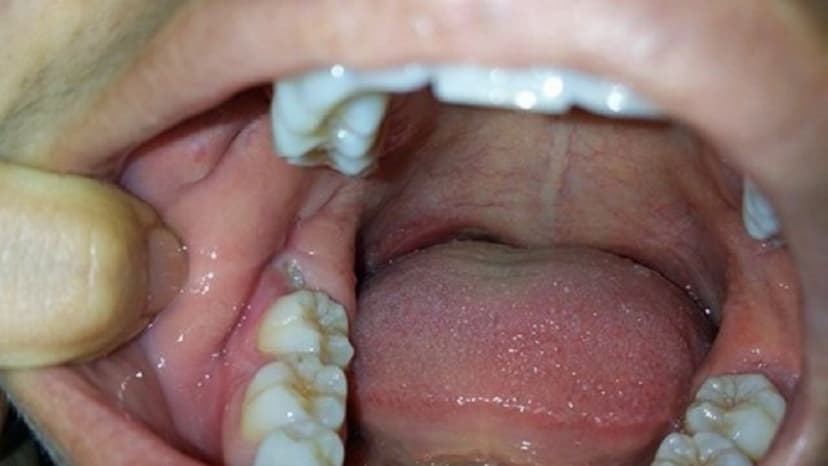

Trường hợp, bệnh nhân bị sưng nướu do răng khôn cấp tính, tình trạng đau nhức dữ dội sẽ xuất hiện. Bên cạnh đó, nếu quan sát, ta sẽ thấy vùng mô nướu sưng tấy. Bệnh nhân có cảm giác đau nhức và càng trầm trọng hơn khi ăn, nhai và nuốt thức ăn. Đặc biệt, vùng nướu quanh răng sẽ tiết dịch mủ, cơ thể bắt đầu xuất hiện tình trạng sốt nhẹ.

Đối với sưng nướu do răng khôn mạn tính, bệnh nhân sẽ thấy bắt đầu những cơn đau âm ỉ từ 1 – 2 ngày. Kéo theo đó, hơi thở của người bệnh sẽ có mùi khó chịu và cũng gặp nhiều có khăn khi ăn, nhai. Thậm chí nghiêm trọng hơn, cơ miệng sẽ không mở được bình thường khi nói chuyện.